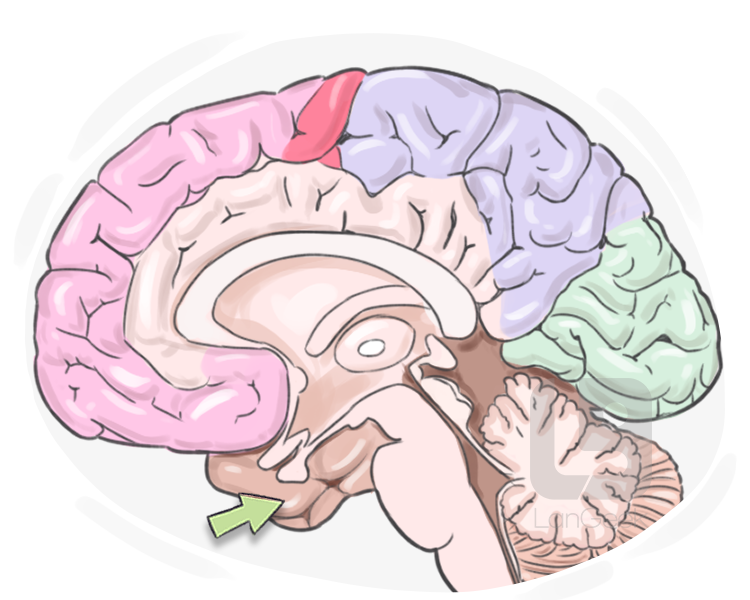

The Temporal Lobes Are Involved In Memory And Emotion Because

Temporal Lobe SpinalCord

Definition Meaning Of Temporal Lobe LanGeek

What Is Temporal Lobe Epilepsy with Pictures